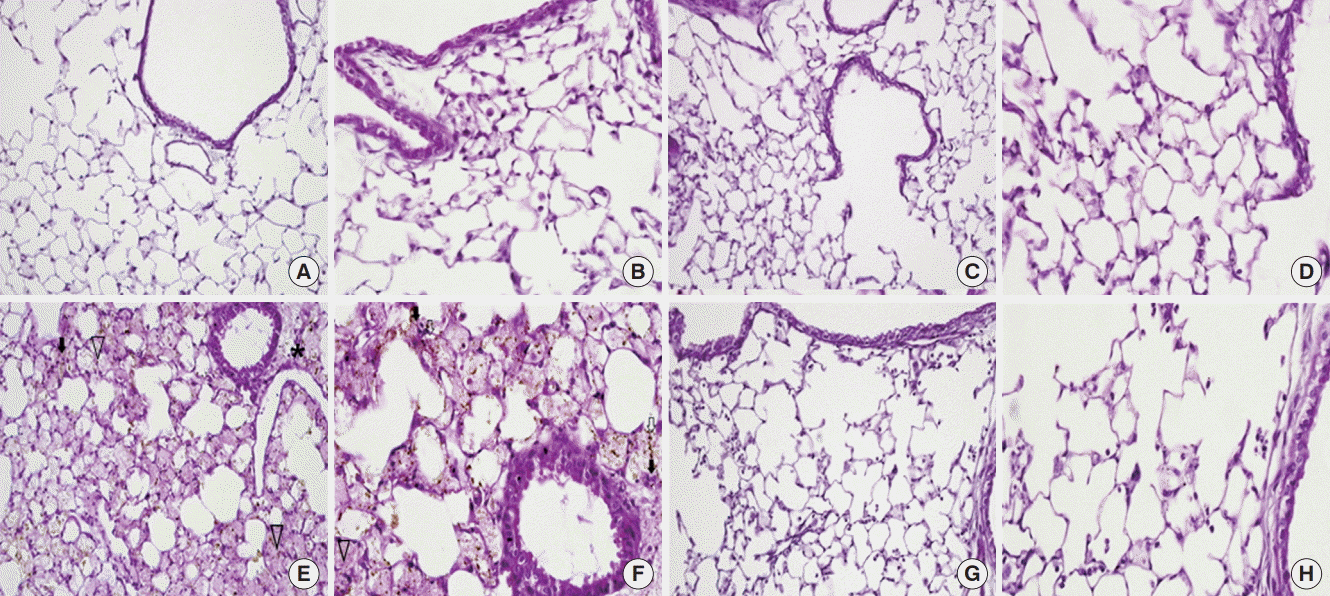

On histological analysis, the CTL (Figure 2A and B) and MSC (Figure 2C and D) groups also had normal parenchymal architecture without any exudates or edema. The LPS group showed an infiltration of inflammatory cells, mainly polymorphonuclear cells, into the alveolar space and interstitium. In addition, there was hemorrhage in the alveolar space (Figure 2E and F). However, the LPS/MSC group had a relatively wellmaintained alveolar space compared to that of the LPS group. Infiltration of inflammatory cells into the alveolar space and edema around the blood vessels decreased while there was almost no hemorrhage or edema in the alveolar space (Figure 2G and H). To quantify the differences, lung injury was scored (Figure 3). LPS groups showed significant increases in lung injury score scores (P<0.05, vs. CTL groups). LPS/MSC groups significantly attenuated the LPS-induced increases in injury scores (P<0.05, vs. LPS groups).

Figure 2.

Light microscopy findings of the lung. (A, B) In the control (CTL) group, the normal parenchymal architecture, including the alveolar septa, alveolar lumen, and capillaries were well preserved. The infiltration of inflammatory cells was not observed. (C, D) In the mesenchymal stem cell (MSC) injected group, the normal pulmonary architecture was well preserved similar to that in the CTL group. (E, F) In the lipopolysaccharide (LPS)-induced acute lung injury group, the pulmonary architecture, including the alveolar septa and alveolar lumen were not preserved. Perivascular edema (asterisk) and intrapulmonary hemorrhage (arrow heads) were observed. The infiltration of inflammatory cells, perivascular cuffing (black arrows), and floating of phagocytes in the alveolar lumen (white arrows) were observed. (G, H) In the MSC injection following LPS induced acute lung injury (LPS/MSC) group, the alveolar septa and alveolar lumen were relatively well preserved. Intrapulmonary hemorrhage and perivascular cuffing was less prominent compared to those of the lungs in the LPS group. The infiltration of inflammatory cells was not observed. (H&E; magnification, A, C, E, G: ×200; B, D, F, H: ×400).